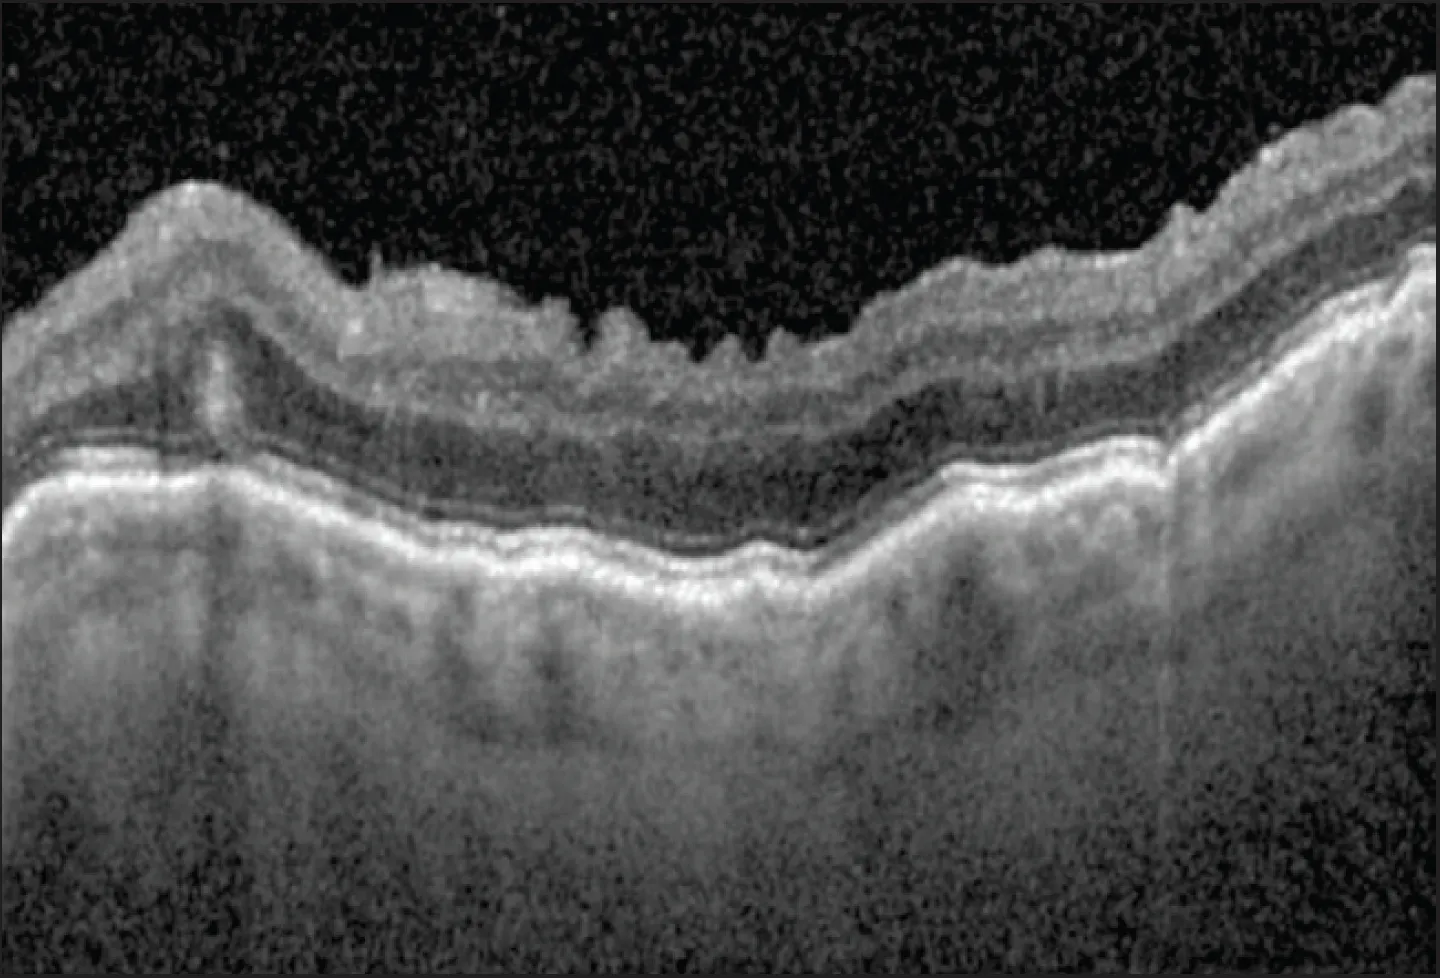

Hypotony maculopathy from persistently low IOP can create retinal and choroidal folds in the macula, which can reduce or distort patients’ central vision. Peaks and valleys in these folds from severe maculopathy are visible on fundus examination, but subtle cases can be difficult to detect on examination. In subtle hypotony maculopathy, OCT of the macula can show chorioretinal folds involving the retinal pigment epithelium and Bruch membrane and, in advanced cases, more extensive folds in the inner retinal layers (Figure 1).3

Figure 1. Significant chorioretinal folds consistent with hypotony maculopathy are visualized using OCT of the macula.